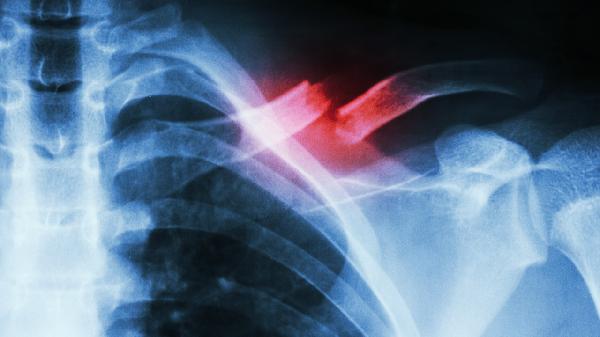

骨质增生cr上片子

骨质增生CR上片子,即进行X线检查时,通过X线片观察到骨质增生的情况。骨质增生是一种常见的疾病,是由于关节退变、劳损或外伤等因素导致的骨骼边缘形成骨性增生物,可发生在各个年龄段。 hzh{displ